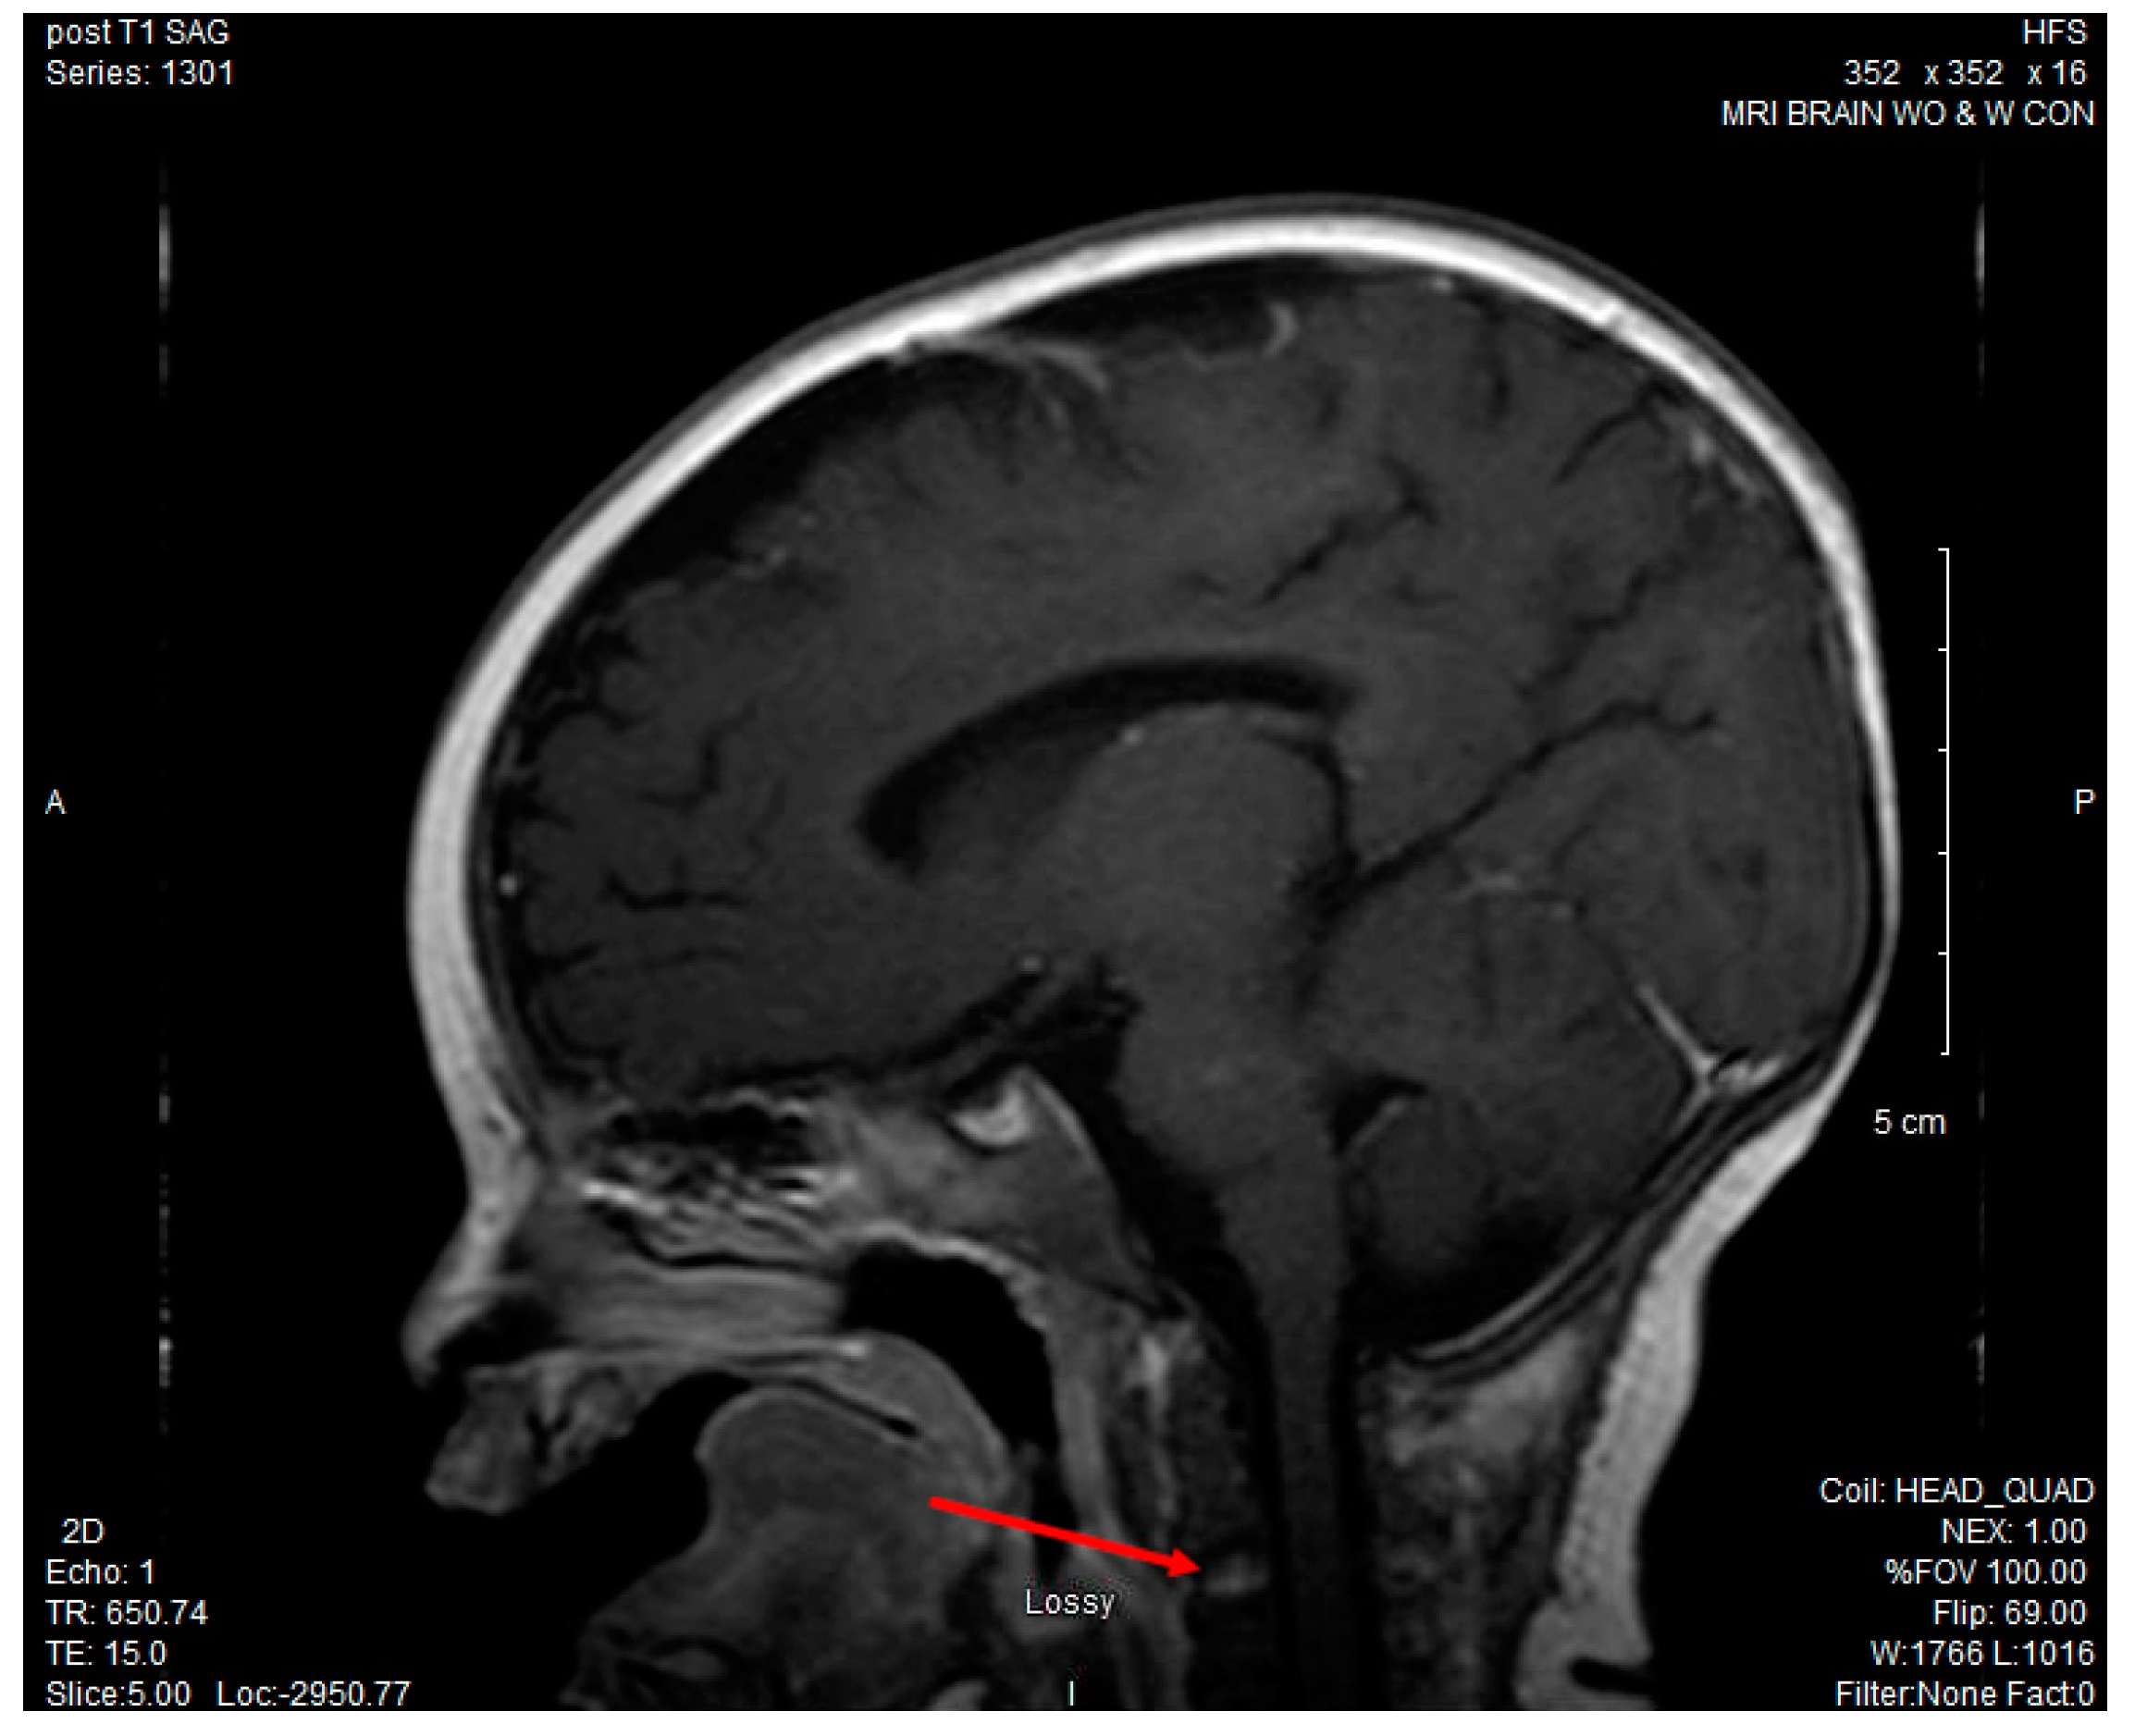

CSF culture grew P. multocida, while both the blood and urine cultures remained negative. Antibiotics were narrowed to ceftriaxone alone for meningitis once susceptibilities were known. Due to continued fussiness and decreased neck movement despite appropriate antibiotic treatment, an MRI of the brain and cervical spine was obtained and revealed leptomeningeal enhancement consistent with meningitis and enhancement of the C3 vertebral body, suggestive of osteomyelitis. (See Figure 1).

Figure 1. Magnetic resonance imaging (MRI) brain with and without contrast: increased T2 enhancement of the C3 vertebral body concerning for osteomyelitis.